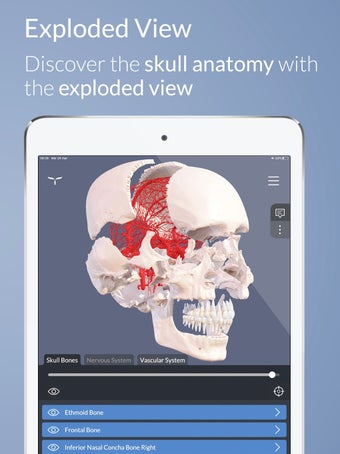

Esta es una aplicación de aprendizaje gratuita, diseñada para ayudarte a entender el cerebro humano y su anatomía y funciones.

Para ayudar en el aprendizaje y la memorización, la aplicación incluye una vasta colección de textos científicos divididos en tres niveles cognitivos, que van desde una visión general hasta definiciones altamente detalladas.